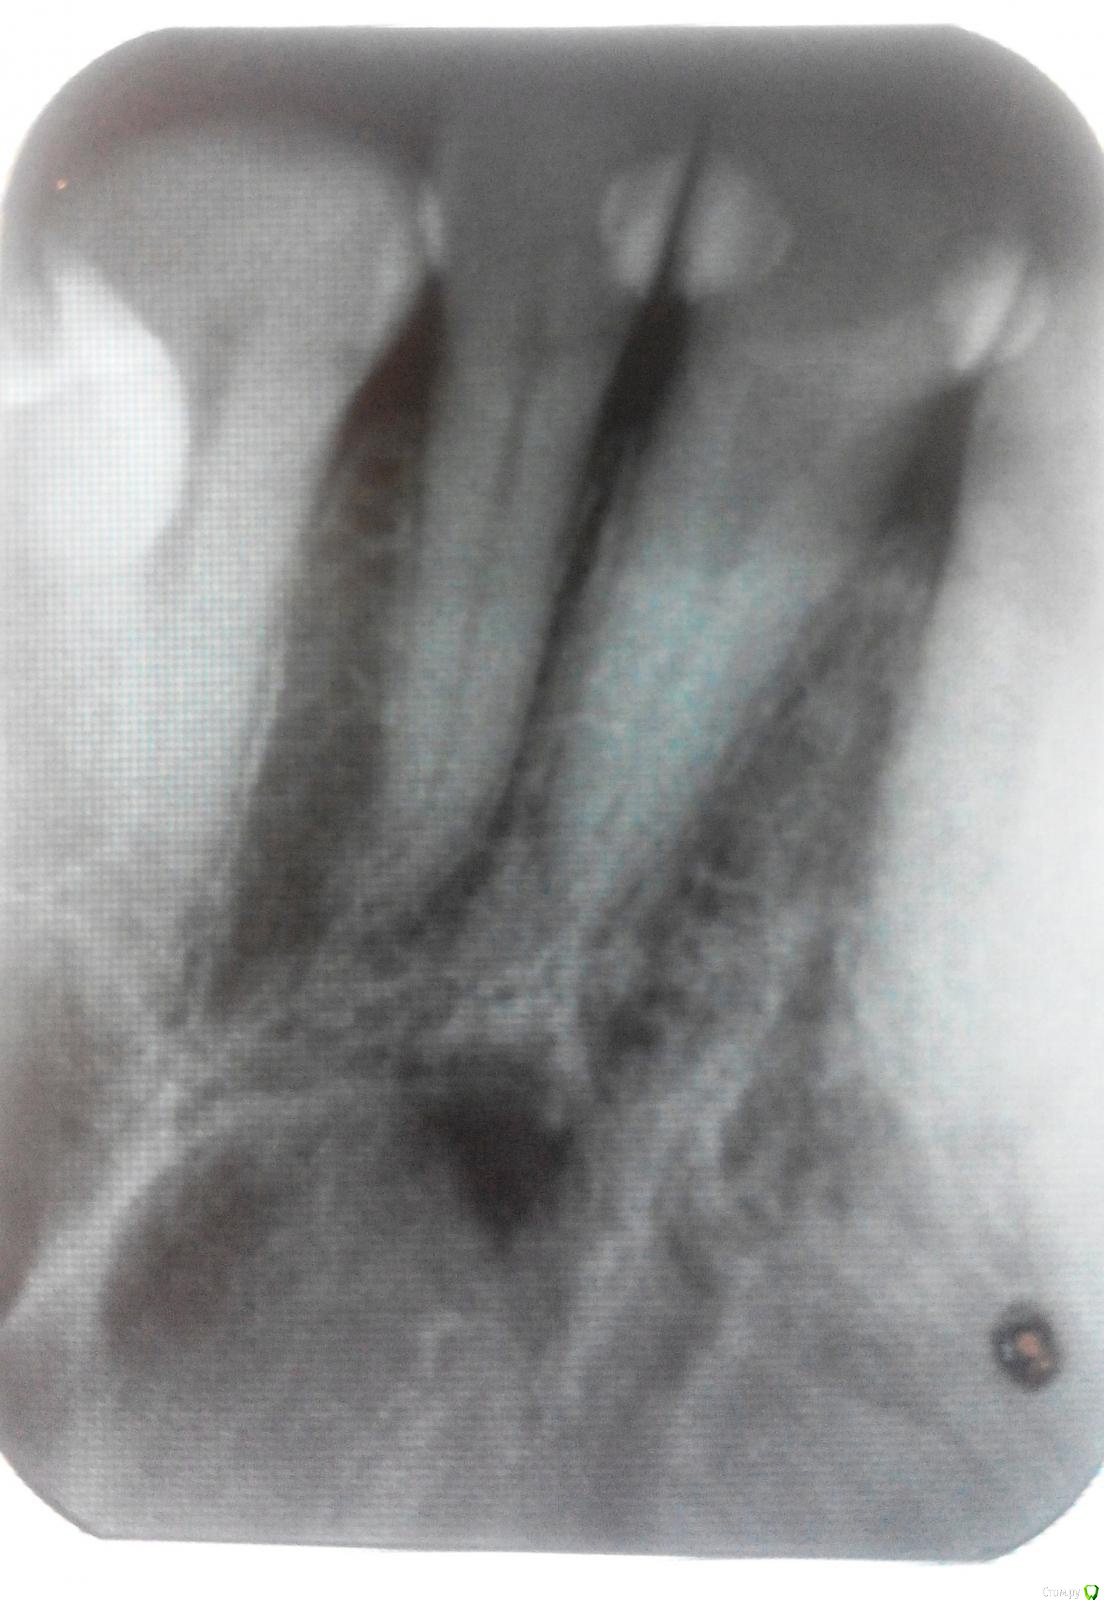

Светлана Л Опубликовано 30 апреля, 2018 Поделиться Опубликовано 30 апреля, 2018 Добрый вечер.Болит верхний первый справа. Зуб ноет, тюкает. Зуб промбированный в промежутках.Боль отдает в десну и в челюсть справа.Начиналось все это зимой как только подмерзала.Потом вроде как утихло.Сделали снимок. https://a.radikal.ru/a40/1804/7f/1031344c12e2t.jpg Врач сказал, периодонтит корневого канала первого зуба.(Ей слова - Разряжение приличное)Дайте совет, с чего начинать - с томограммы? искать хорошего стоматолога?Посмотрите снимок пожалуйста, может не все так страшно? Ссылка на комментарий